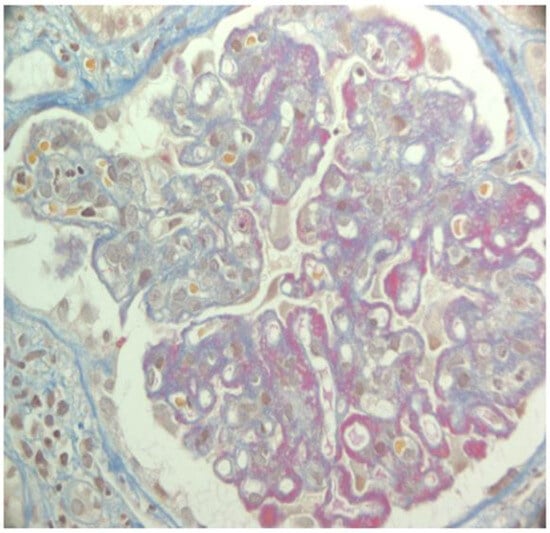

- Recurrence of lupus nephritis and outcomes and therapy

- Weening, J.J.; D’Agati, V.D.; Schwartz, M.M.; Seshan, S.V.; Alpers, C.E.; Appel, G.B.; Balow, J.E.; Bruijn, J.A.; Cook, T.; Ferrario, F.; et al. The Classification of Glomerulonephritis in Systemic Lupus Erythematosus Revisited. J. Am. Soc. Nephrol. 2004, 15, 241–250. [Google Scholar] [CrossRef]

- Goral, S.; Ynares, C.; Shappell, S.B.; Snyder, S.; Feurer, I.D.; Kazancioglu, R.; Fogo, A.B.; Helderman, J.H. Recurrent Lupus Nephritis in Renal Transplant Recipients Revisited: It Is Not Rare1. Transplantation 2003, 75, 651–656. [Google Scholar] [CrossRef]

- Nyberg, G.; Blohmé, I.; Persson, H.; Olausson, M.; Svalander, C. Recurrence of SLE in Transplanted Kidneys: A Follow-up Transplant Biopsy Study. Nephrol. Dial. Transplant. 1992, 7, 1116–1123. [Google Scholar]

- Weng, F.; Goral, S. Recurrence of Lupus Nephritis after Renal Transplantation: If We Look for It, Will We Find It? Nat. Clin. Pract. Nephrol. 2005, 1, 62–63. [Google Scholar] [CrossRef]

- Norby, G.E.; Strøm, E.H.; Midtvedt, K.; Hartmann, A.; Gilboe, I.-M.; Leivestad, T.; Stenstrøm, J.; Holdaas, H. Recurrent Lupus Nephritis after Kidney Transplantation: A Surveillance Biopsy Study. Ann. Rheum. Dis. 2010, 69, 1484–1487. [Google Scholar] [CrossRef]